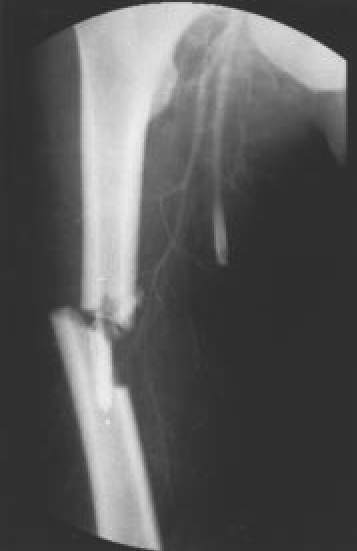

| Fig. 7D.: Arteriografía de control tras la intervención, apreciándose el restablecimiento del flujo arterial |